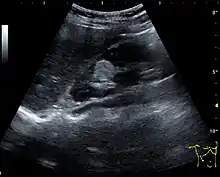

One of the primary indications for referral to US evaluation of the kidneys is evaluation of the urinary collecting system. Enlargement of the urinary collecting system is usually related to urinary obstruction and can include the pelvis, the calyces and the ureter. Hydronephrosis is seen as an anechoic fluid-filled interconnected space with enhancement within the renal sinus, and normally, the dilated pelvis can be differentiated from the dilated calyces.[1]

Figure 13. Hydronephrosis due to ureteropelvic junction obstruction in a pediatric patient.[1]

Several conditions can result in urinary obstruction. In both adults and children, masses, such as abscesses and tumors, can compress the ureter. In children, hydronephrosis can be caused by ureteropelvic junction obstruction, ectopic inserted ureter, primary megaureter and posterior urethral valve (Figure 13). In the latter, both kidneys will be affected. In adults, hydronephrosis can be caused by urolithiasis, obstructing the outlet of the renal pelvis or the ureter, and compression of the ureter from, e.g., pregnancy and retroperitoneal fibrosis. Urolithiasis is the most common cause of hydronephrosis in the adult patient and has a prevalence of 10%–15%.[1]

The hydronephrosis is typically graded visually and can be divided into five categories going from a slight expansion of the renal pelvis to end-stage hydronephrosis with cortical thinning (Figure 15). The evaluation of hydronephrosis can also include measures of calyces at the level of the neck in the longitudinal scan plane, of the dilated renal pelvis in the transverse scan plane and the cortical thickness, as explained previously (Figure 16 and Figure 17).[1]